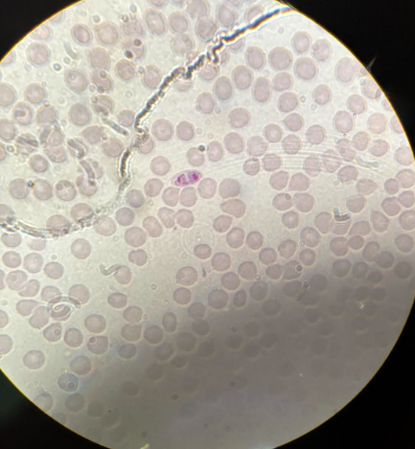

plasmodium ovale stadia schizogonii krwinkowej

plasmodium ovale stadia schizogonii krwinkowej